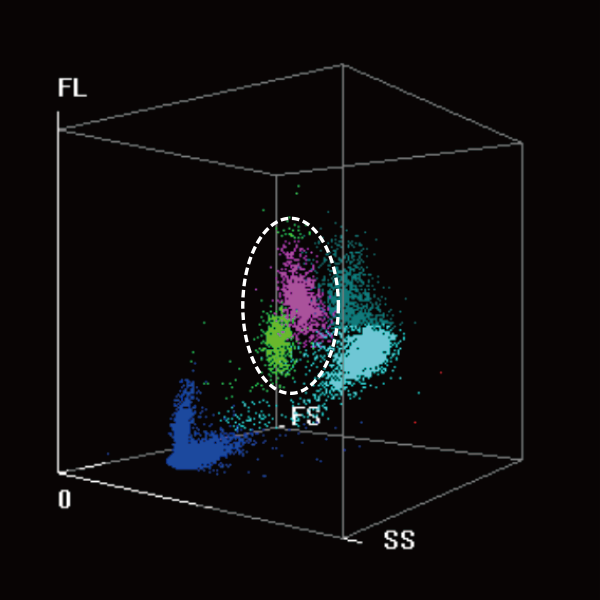

High Sensitivity and Specificity of Blast Flagging Capability for Preliminary Screening

The coordinated analysis technology of WNB and DIFF scattergarms give sensitive alerts for РђюBlasts" with high specificity to reduce unnecessary labor-intensive manual microscopy.

DIFF 3D scattergram

Coordinated analysis

WNB 3D scattergram

Abn. Lymph/blast?

Abn. Promyelocyte/blast?

The detection concentration is as low as 0.03├Ќ10?/L